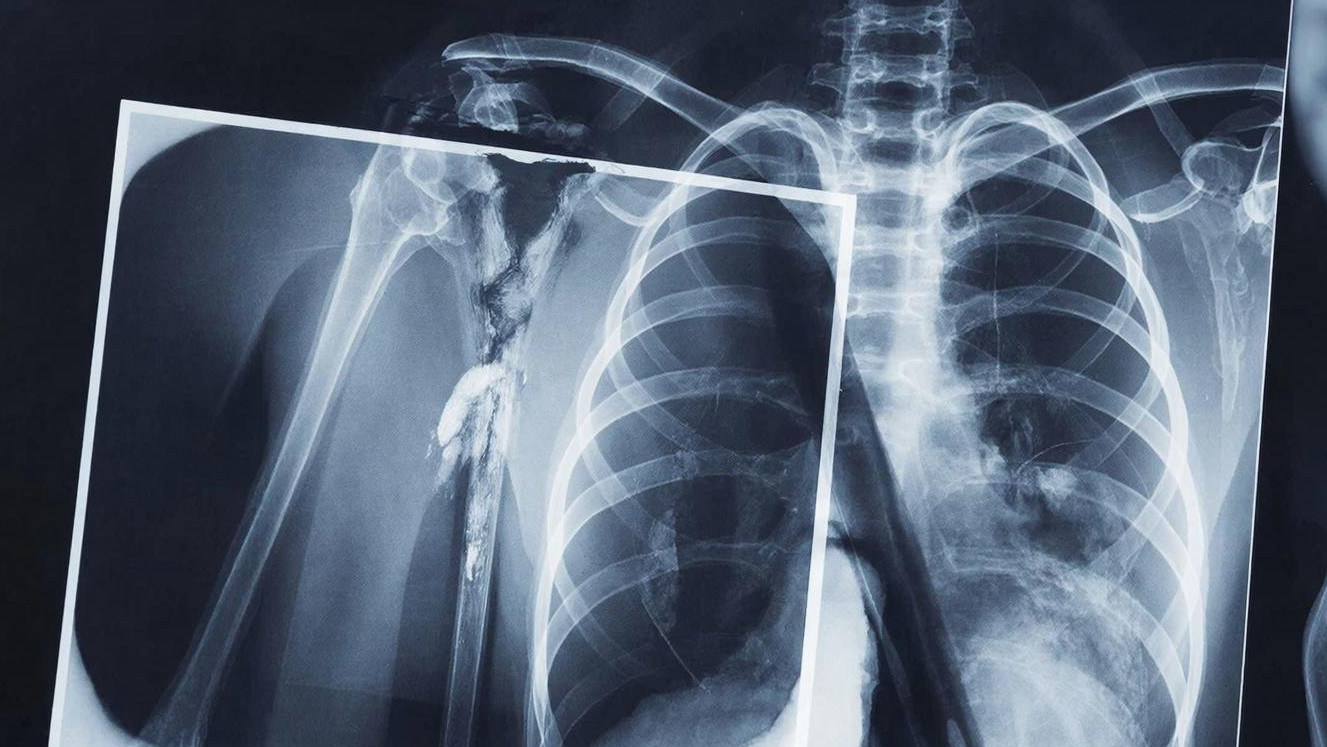

За прошлый год нейросети помогли кубанским врачам в расшифровке более 900 тысяч рентген-исследований. Новую технологию уже внедрили в цифровые рентген-аппараты, маммографы и флюографы по всему Краснодарскому краю.

Полностью врача система не заменяет. Искусственный интеллект выделяет и детализирует область снимка, на которую специалист должен обратить особое внимание. В результате — экономия времени по меньшей мере в 3 раза. Вместо 15 минут врач тратит на изучение снимка максимум 5 минут.

Наиболее массовое рентген-исследование с применением нейросетей на Кубани — флюорография. За 2025 год система проанализировала около 400 тысяч исследований.